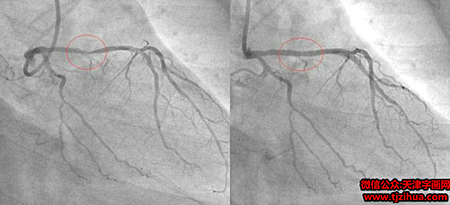

这位 Hakim让他自己在家中做一个食疗,他吃了一个月。一个月后他去同一家医院做检查,发现三条血管干干净净,原来堵塞的地方已经全通了。他是一位虔诚的回教徒,为了让更多的人受益,他把自己的经验放在网上分享,他的前后两张血管照片也放了在网上,在照片中,服用食疗之前与之后的分别连普通人都看的出來